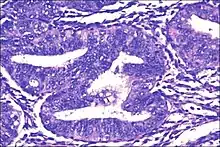

| Micrograph showing simple endometrial hyperplasia, where the gland-to-stroma ratio is preserved but the glands have an irregular shape and/or are dilated. Endometrial biopsy. H&E stain. | |

Endometrial hyperplasia is a condition of excessive proliferation of irregular size and shaped endometrial glands in the uterus, without significant cytoplasmic atypia.[1]

- Endometrial hyperplasia (simple or complex) - Irregularity and cystic expansion of glands (simple) or crowding and budding of glands (complex) without worrisome changes in the appearance of individual gland cells. In one study, 1.6% of patients diagnosed with these abnormalities eventually developed endometrial cancer.[7]